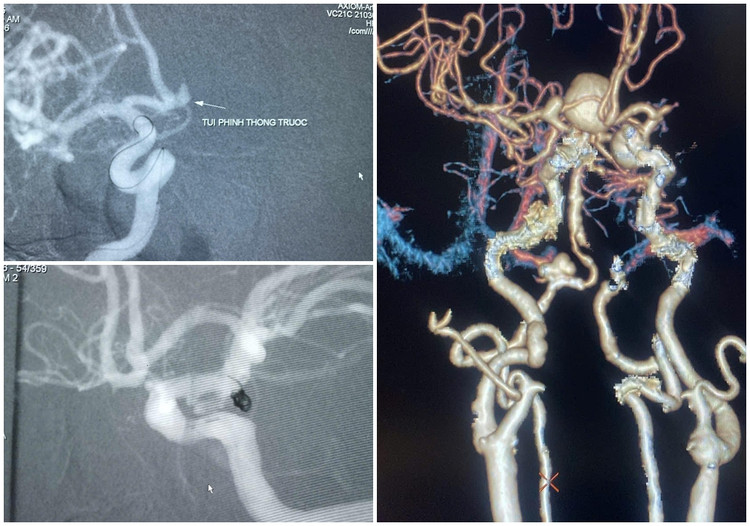

| Hình ảnh các túi phình mạch não được kíp bác sĩ khoa Chẩn đoán hình ảnh can thiệp nút coil - Ảnh BVCC |

Có những trường hợp phình mạch não may mắn phát hiện được chúng tôi can thiệp nút mạch kịp thời, xuất viện sau 1-2 ngày. Tuy nhiên, có không ít các ca nhập viện muộn, chậm trễ nên việc điều trị phục hồi rất chậm, để lại di chứng thần kinh – vận động, ảnh hưởng nặng nề đến cuộc sống về sau, thậm chí tử vong ngay khi đến viện. Việc phát hiện sớm, điều trị kịp thời là vô cùng quan trọng đối với những bệnh nhân đột quỵ”.